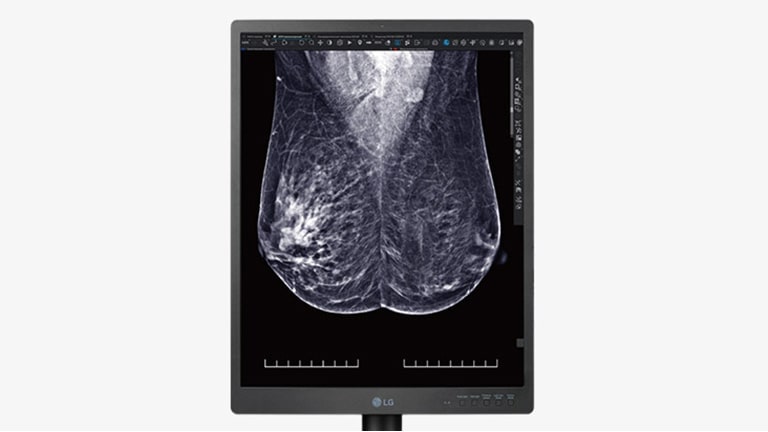

High resolution display for breast imaging

High Definition Imaging

Diagnostic Monitor 21HQ613D displays radiological images, including full field digital mammography and digital breast tomosynthesis, with a brightness of 1,100 cd/m² and a contrast ratio of 1,800:1. Moreover, this monitor showcases vivid colour, high definition mammography and breast tomosynthesis images including breast MRI, CT scans and ultrasound, ensuring versatile performance across various medical imaging modalities.

Diagnostic Monitor 21HQ613D displays radiological images, including full field digital mammography and digital breast tomosynthesis, with a brightness of 1,100 cd/m² and a contrast ratio of 1,800:1.

Multi-resolution mode

Set the resolution mode to fit your needs

The various resolution modes (5/3/2MP) of the 21HQ613D allow users to customise their resolution to better fit their respective needs.